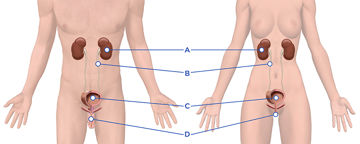

Das Harnsystem ist verantwortlich für die Beseitigung von Abfallprodukten und überschüssiger Flüssigkeit aus dem Körper, indem Urin gebildet und ausgeschieden wird.

Das Harnsystem ist verantwortlich für die Beseitigung von Abfallprodukten und überschüssiger Flüssigkeit aus dem Körper, indem Urin gebildet und ausgeschieden wird.

Das Harnsystem ist verantwortlich für die Beseitigung von Abfallprodukten und überschüssiger Flüssigkeit aus dem Körper, indem Urin gebildet und ausgeschieden wird.

Die Blase ist ein muskulöses Hohlorgan im Becken, knapp über und hinter dem Schambein. Die Blase hat zwei Hauptfunktionen: die Speicherung und Entleerung des Urins.

Erkrankungen, Altern oder Verletzungen können zu einem Verlust der Blasenkontrolle führen, indem sie die Fähigkeit der Blase beeinträchtigen, Urin zu speichern und zu entleeren.